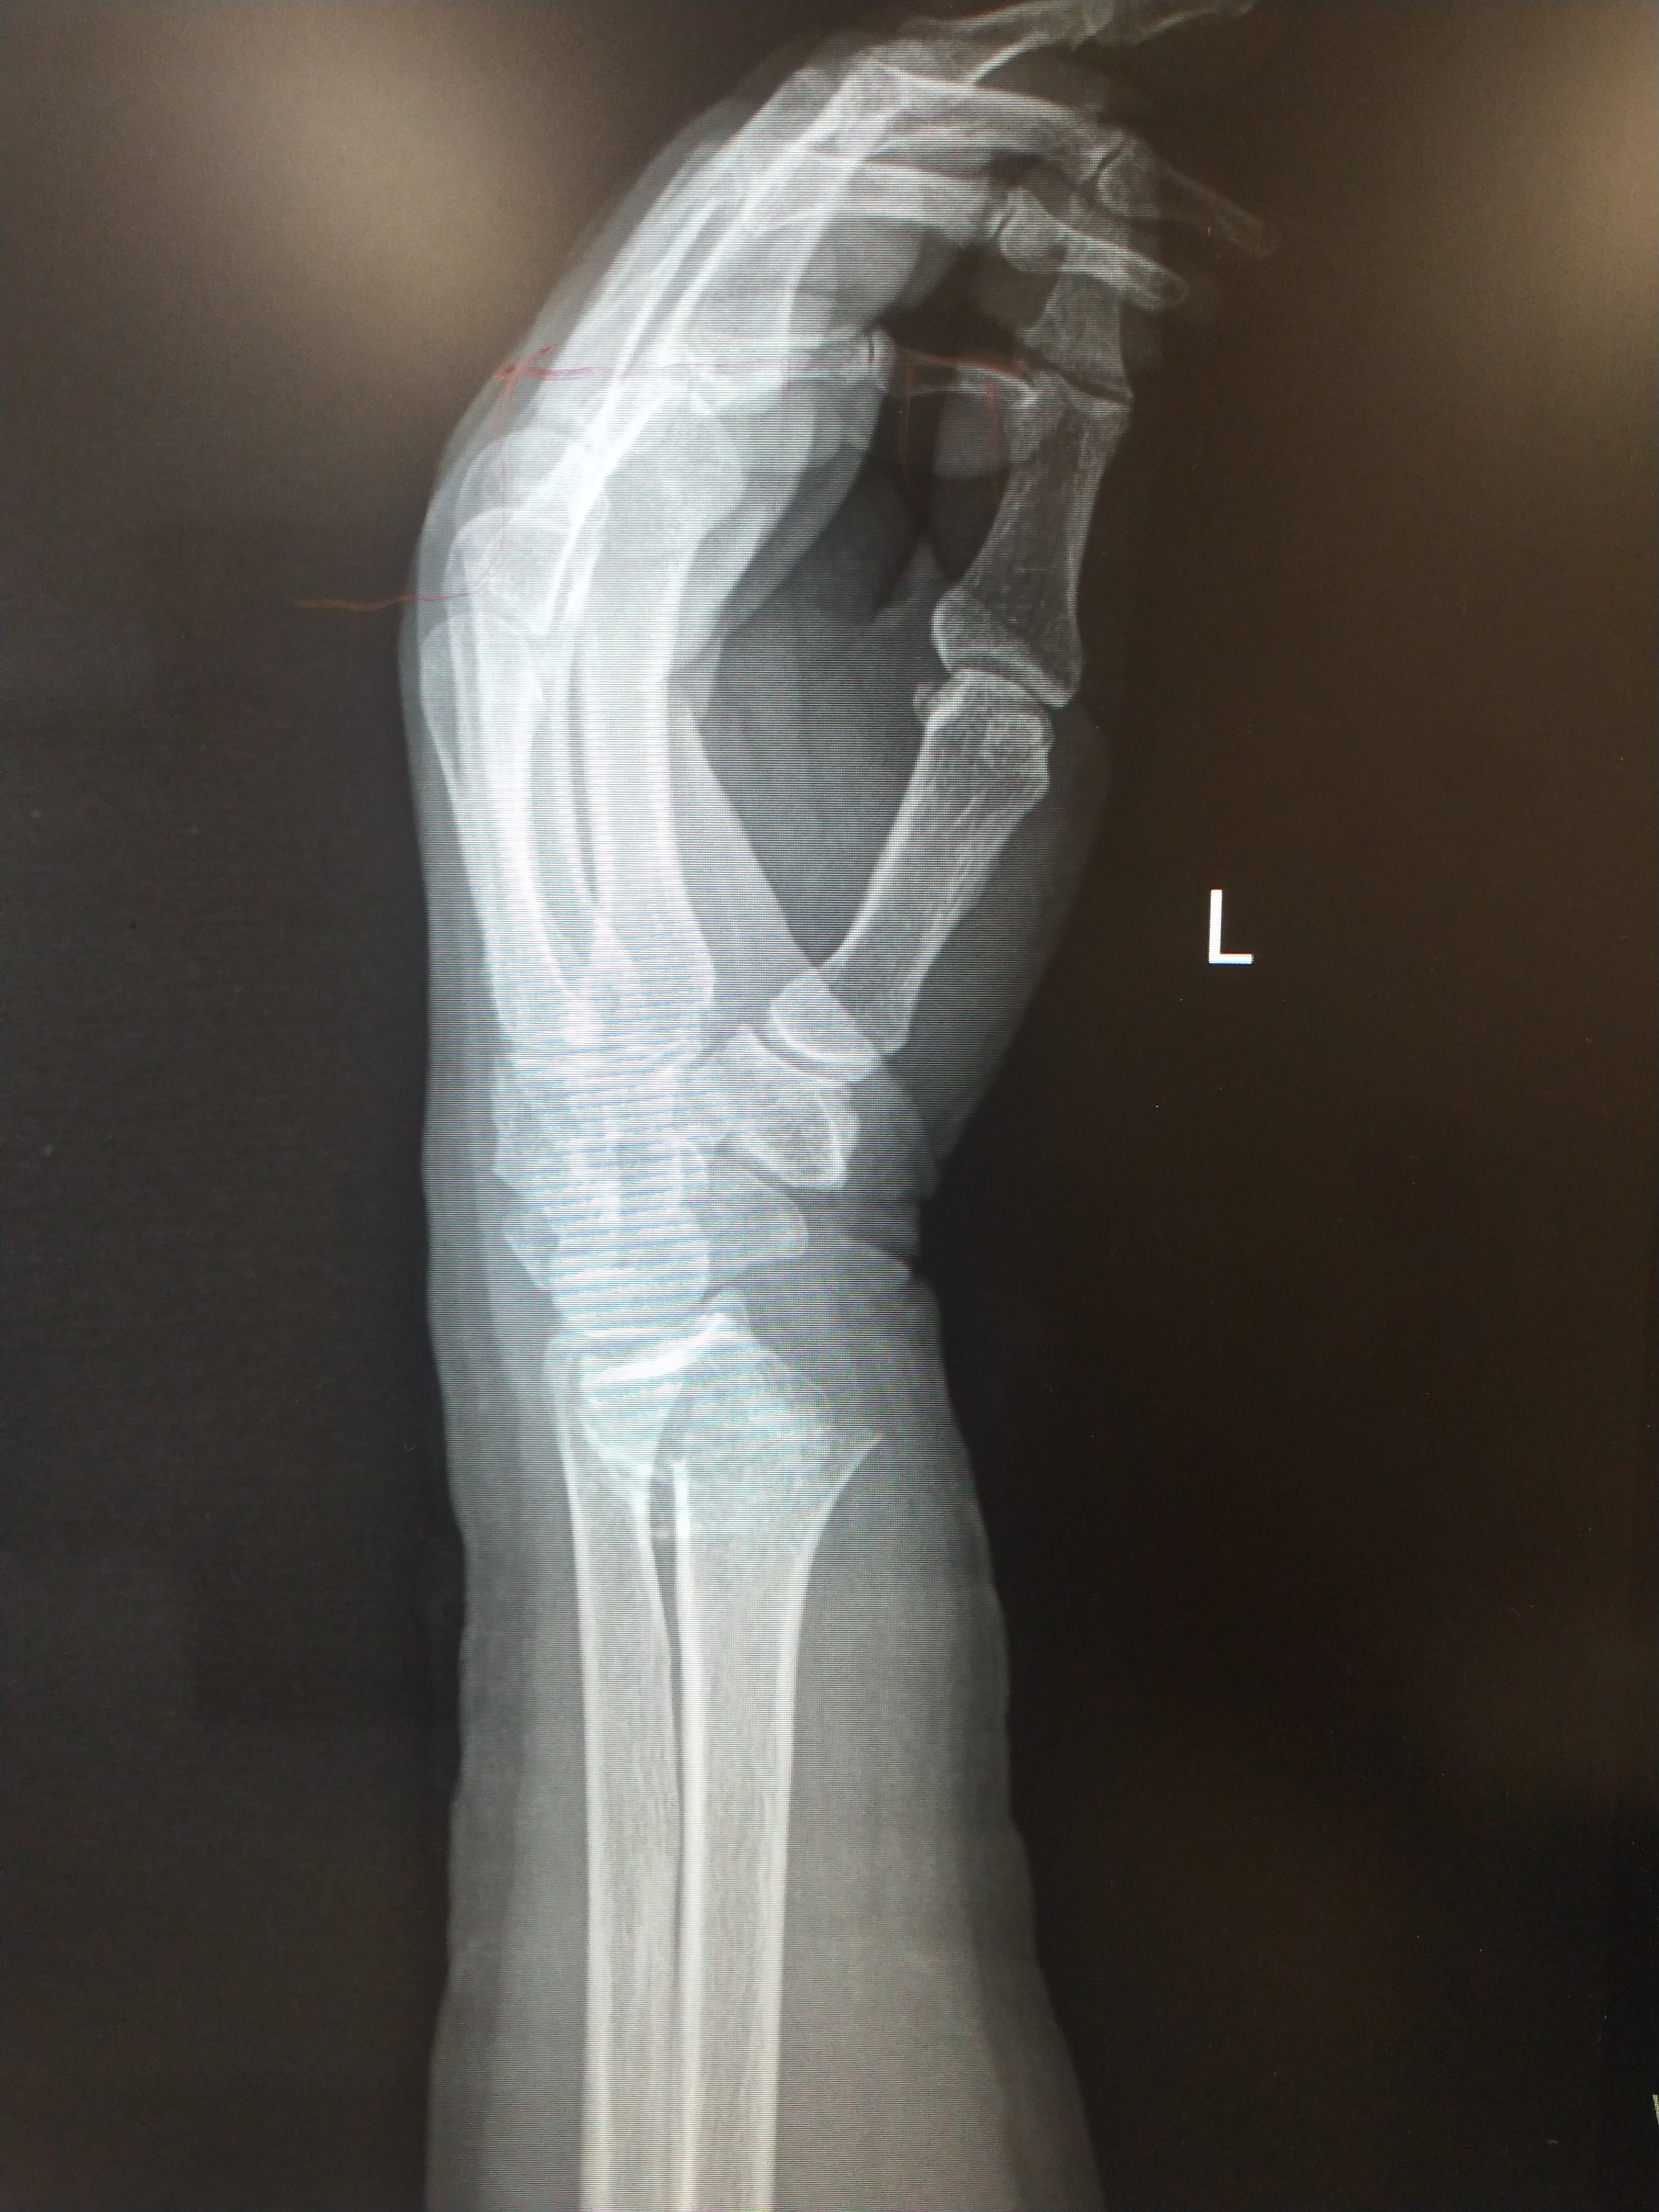

左腕关节ap与侧视的x射线图像库存照片 图片包括有左腕关节ap与侧视的x射线图像

左腕关节ap与侧视的x射线图像库存图片 图片包括有左腕关节ap与侧视的x射线图像